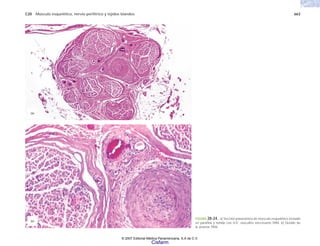

FIGURA 2-1. Glóbulos rojos de un caso de anemia de células falciformes. (Cortesía del Dr. Joaquín Carrillo).